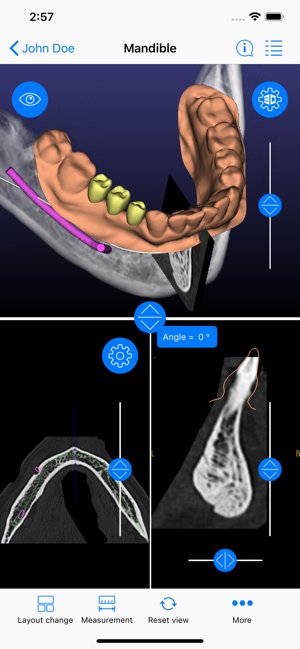

ICX-Magellan X is a cloud-based Software concept used for CBCT-Analysis and to create Implant-Treatment plans.

The ICX-Magellan X App completes this System primarily regarding communication, treatment-plans that were prepared at the pc can be shared with other users in real-time, commented, changed or confirmed.

The App can be integrated supporting any workflow; existing treatment-plans can be recalled, edited or used for patient-education anywhere anytime.